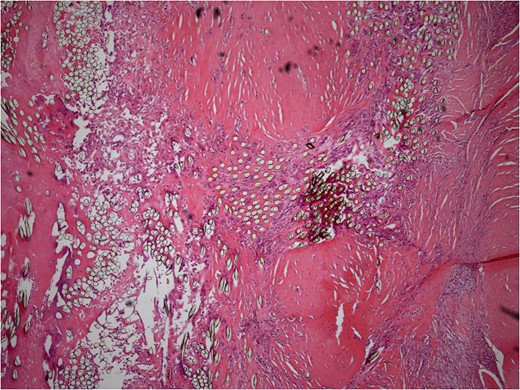

He underwent surgery to explore the tendon where an irregular, cystic, fibrofatty lesion was identified within the tendon (Figs 3–5). This was successfully resected and sent for histology which showed a florid granulomatous and histiocytic response to the suture material, in keeping with a suture granuloma (Figs 6 and 7). There was histological evidence of the abscess extending into the muscle (Fig. 8).

Low power histology slide showing foreign body giant cell reaction to suture material.